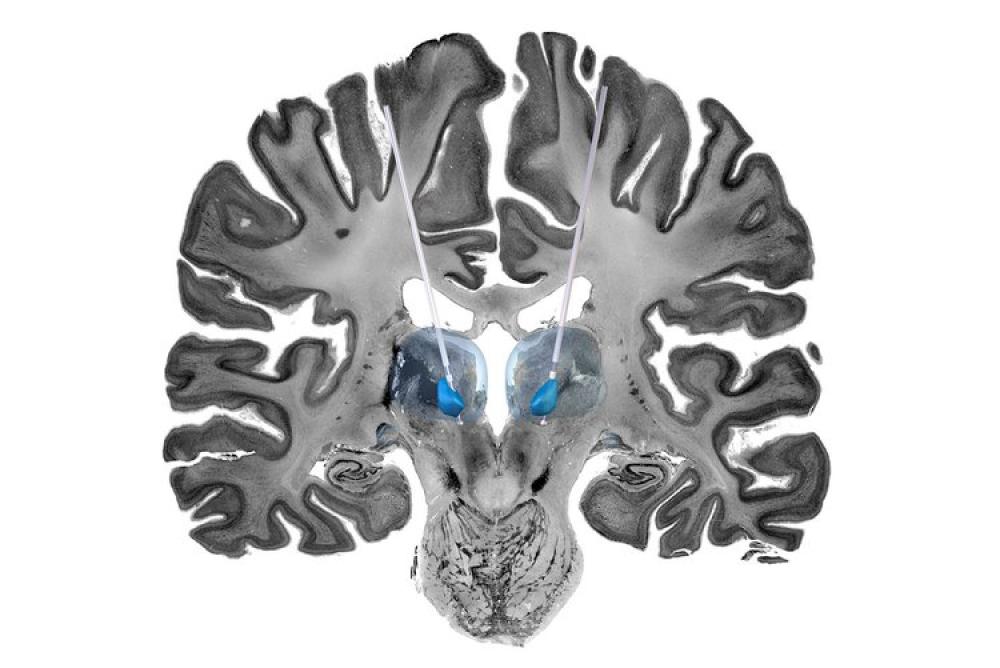

GOSH Staff Network’s favourite: Stimulating the brain, an evolving treatment for children with drug-resistant seizures

Entered by Rory Piper, Lewis Spitz Surgeon Scientist PhD Student, this image resembling the features of a lion has captured the cross-section of a simulated brain used to help study potential treatments for epilepsy in children.

Deep brain stimulation (DBS) is a type of brain surgery that uses electrical pulses to change the way the brain works. This treatment can be helpful in certain brain conditions, such as epilepsy, in which the brain's electrical activity is abnormal and needs to be corrected or changed. Here, a representative cross-section of the brain (looking from front to back) shows two DBS wires implanted in the thalamic regions (blue), which are parts of the brain involved in the routing of electrical signals.